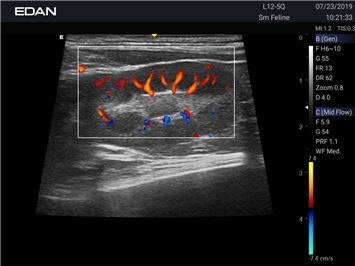

Недопплеровская визуализация кровотока:

Да

Направленный энергетический допплер:

Энергетический допплер:

Цветовой допплер: